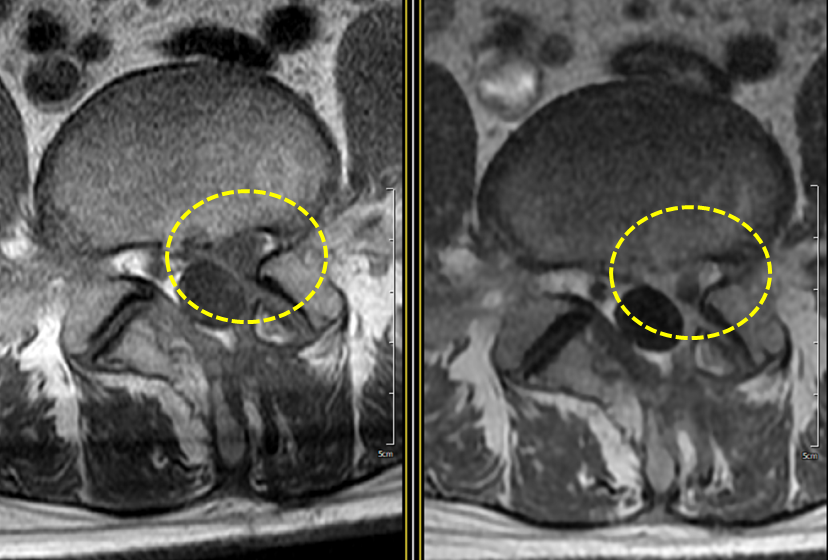

허리디스크, MRI, 조영제의 중요성에 대하여

MRI 촬영 시 조영제의 중요성 MRI(자기공명영상)는 인체 내부 구조를 상세하게 시각화하는 강력한 진단 도구입니다. 그러나 MRI는 기본적으로 수분 함량이 높은 조직을 구분하는 데 최적화되어 있기 때문에, 조영제를 사용함으로써 영상의 선명도와 진... thumbnail 1 summary